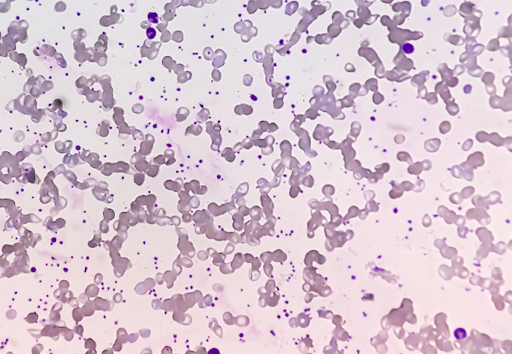

抗体が赤血球の表面にくっつくと赤血球同士が固まったり、体の免疫システムが作動し赤血球を異物と判断して破壊処理します。

赤血球がお互いに固まると血液の流れが悪くなりますし、破壊されれば貧血が起こってしまいます。

血液の検査では赤血球がくっついていることや抗体を確認します。